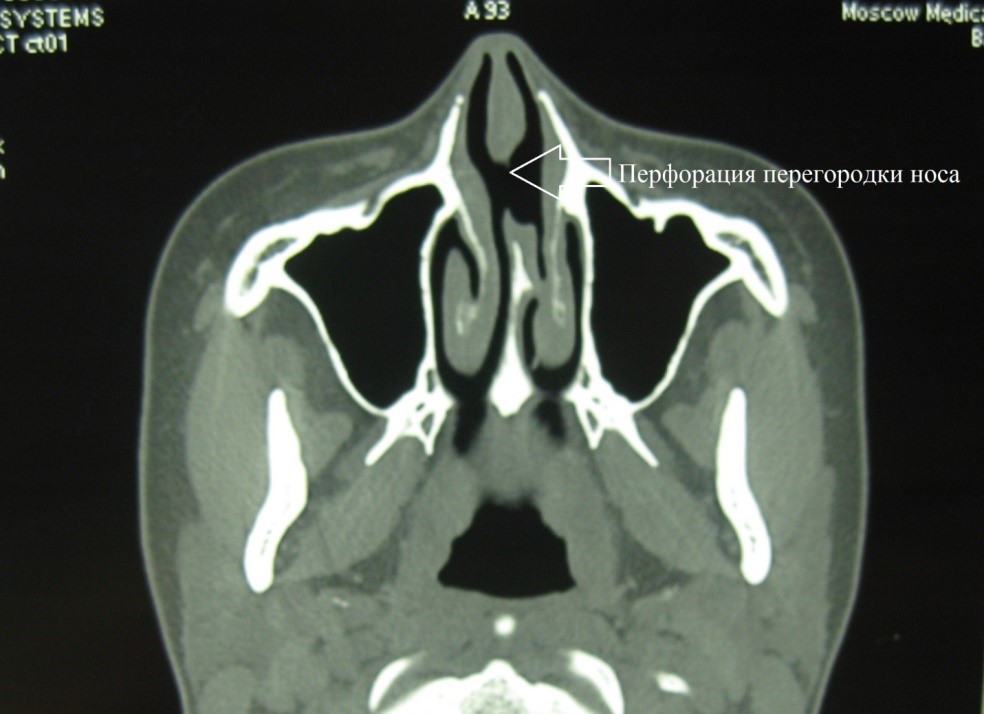

For those that are determined to be medically cleared for surgery, the anatomical location and size of the perforation must be determined. This is often done with a combination of a CT scan of the sinuses without contrast and an endoscopic evaluation by an Ear Nose and Throat doctor. Once dimensions are obtained the surgeon will decide if it is possible to close the perforation. Multiple approaches to access the septum have been described in the literature. While sublabial and midfacial degloving approaches have been described, the most popular today is the rhinoplasty approach. This can include both open and closed methods. The open method results in a scar on the columella, however, it allows for more visibility to the surgeon. The closed method utilizes an incision all on the inside of the nose. The concept behind closure includes bringing together the edges of mucosa on each side of the perforation with minimal tension. An interposition graft is also often used. The interposition graft provides extended stability and also structure to the area of the perforation. Classically, a graft from the scalp utilizing temporalis fascia was used. Kridel, et al., first described the usage of acellular dermis so that no further incisions are required; they reported an excellent closure rate of over 90 percent. Overall perforation closure rates are variable and often determined by the skill of the surgeon and technique used. Often surgeons who claim a high rate of closure choose perforations that are easier to close. An open rhinoplasty approach also allows for better access to the nose to repair any concurrent nasal deformities, such as saddle nose deformity, that occur with a septal perforation.